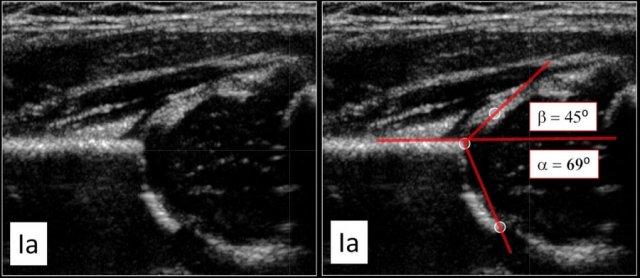

Type I

Hãy loại I có góc alpha lớn hơn 60 độ và được coi là bình thường.

Mặc dù có sự phân biệt giữa loại Ia và Ib nhưng điều này không có ý nghĩa lâm sàng.

Type Ia

Kết quả kiểm tra cho thấy hình thái tốt của mái ổ cối xương với bờ xương góc sắc nét.

Không có vấn đề gì trong việc xác định bờ ngoài của mái ổ cối xương.

Chỏm xương đùi được bao phủ tốt bởi mái sụn và viền sụn.

Góc alpha trên 60 độ và góc beta thấp hơn nhiều so với 55 độ.